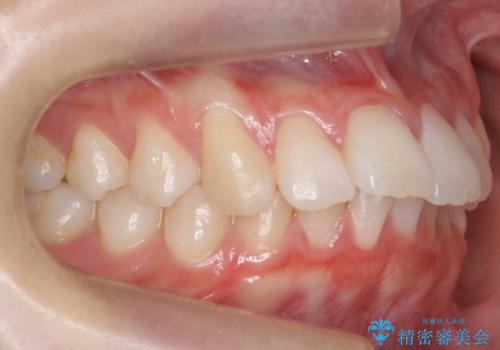

ハーフリンガル 犬歯のねじれ 歯根の外部吸収している歯を抜歯

- 前歯のねじれを主訴に来院。

矯正治療で右下を抜歯し、スペースを天然の歯でつめる矯正治療を行いました。

上顎前歯も唇側傾斜しておらず、もともと叢生が多くない状態で上下左右を抜歯した上、リンガルで治療を行なったため、多少治療期間がかかりました。